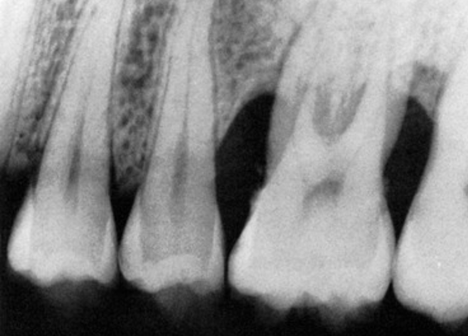

Diagnóstico por Imagem Digital

Tomografias e radiografias digitais para avaliar a perda óssea com precisão milimétrica antes de iniciar qualquer procedimento.